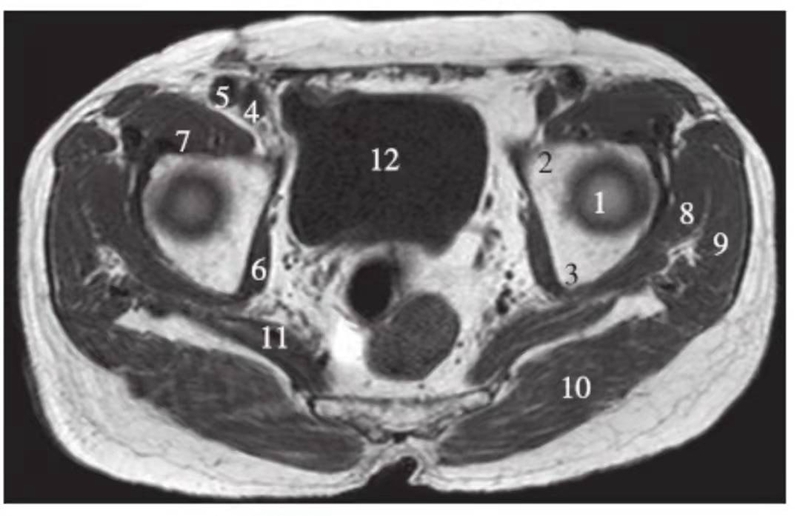

正常髋关节股骨头上缘层面T1WI像

1.股骨头;2.耻骨;3.坐骨;4.股静脉;5.股动脉;6.闭孔内肌;7.髂腰肌;8.臀小肌;9.臀中肌;10.臀大肌;11.梨状肌;12.膀胱

正常髋关节经股骨头中心层面T1WI像

1.股骨头;2.耻骨;3.坐骨;4.股静脉;5.股动脉;6.闭孔内肌;7.髂腰肌;8.臀小肌;9.臀中肌;10.臀大肌;11.膀胱